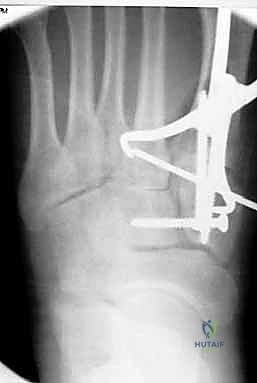

1. الرد المفتوح والتثبيت الداخلي (ORIF - Open Reduction and Internal Fixation)

هذا هو الإجراء الكلاسيكي والأكثر شيوعاً. يهدف إلى إعادة العظام إلى مكانها الطبيعي (الرد) وتثبيتها باستخدام معدات طبية (مسامير، شرائح، أو أسلاك) حتى تلتئم الأربطة والعظام.

4. التثبيت (Fixation): يتم تثبيت العظام باستخدام مسامير معدنية خاصة (Solid or Cannulated Screws) تعبر المفاصل لتثبيتها بإحكام. في بعض الحالات، يتم استخدام شرائح معدنية صغيرة للحفاظ على الاستقرار.

5. مسمار ليزفرانك: الخطوة الأهم هي وضع "مسمار ليزفرانك" (Lisfranc Screw) الذي يمر من العظم المسماري الإنسي إلى قاعدة المشط الثاني، لتعويض وظيفة الرباط الممزق.

6. الإغلاق: يتم إغلاق الشقوق الجراحية بعناية تجميلية ووضع القدم في جبيرة لحمايتها.